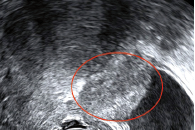

QUIZZ IMAGE 190

Une image à chaque étage par Joël Créquat Contexte cliniquePatiente de 35 ans sans enfant et sans antécédent particulier.Elle n’a pas de contraception. Elle consulte pour dysménorrhée, algies diffuses, dyspareunie progressive, et dysurie menstruelle d’apparition récente.L’examen clinique retrouve une masse annexielle droite, vraisemblablement ovarienne et une sensibilité pelvienne générale.Une échographie est demandée. Voici les résultats…